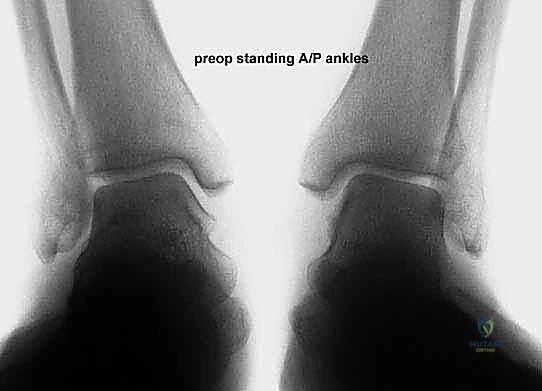

التصوير الشعاعي:

* الأشعة السينية (X-rays) مع تحمل الوزن: ضرورية لتقييم درجة انهيار القوس وزوايا العظام (مثل زاوية تالونافيكولار Meary's Angle).